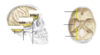

Name of the structure which separates the two cerebral hemispheres